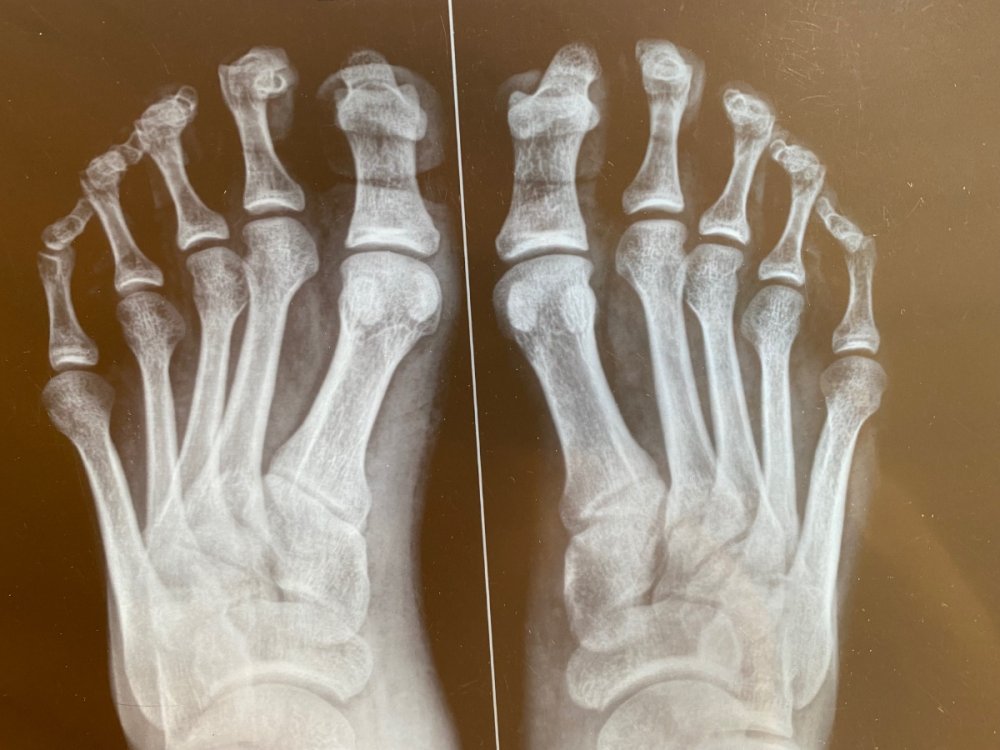

Добрый день! Проходил обследования в гос. учреждениях и платных больницах, был выставлен диагноз «молоточкообразная контрактура пальцев обеих стоп; высокосводчатая стопа». В военкомате был направлен на подтверждение диагноза в областную больницу, где был выставлено иное заключение (на фото). Также прикрепил результаты рентгена. На какую категорию годности я могу претендовать сейчас?

IMG_1209.jpeg

IMG_1210.jpeg

IMG_1212.jpeg

IMG_1214.jpeg

IMG_1207.jpeg